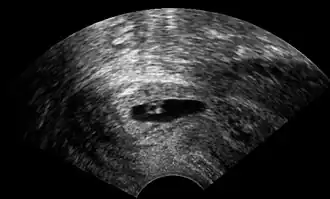

| Ultrassonografia vaginal de uma gravidez cervical com idade gestacional de cinco semanas.[1] | |

O diagnóstico é feito em gestantes assintomáticas, seja pela inspeção que mostra um colo uterino azulado, seja, mais comumente, por ultrassonografia obstétrica. Um sintoma inespecífico típico é o sangramento vaginal durante a gravidez. O ultrassom mostrará a localização do saco gestacional no colo, enquanto a cavidade uterina permanece “vazia”. A gravidez cervical pode ser confundida com um aborto espontâneo quando o tecido da gravidez passa pelo colo.